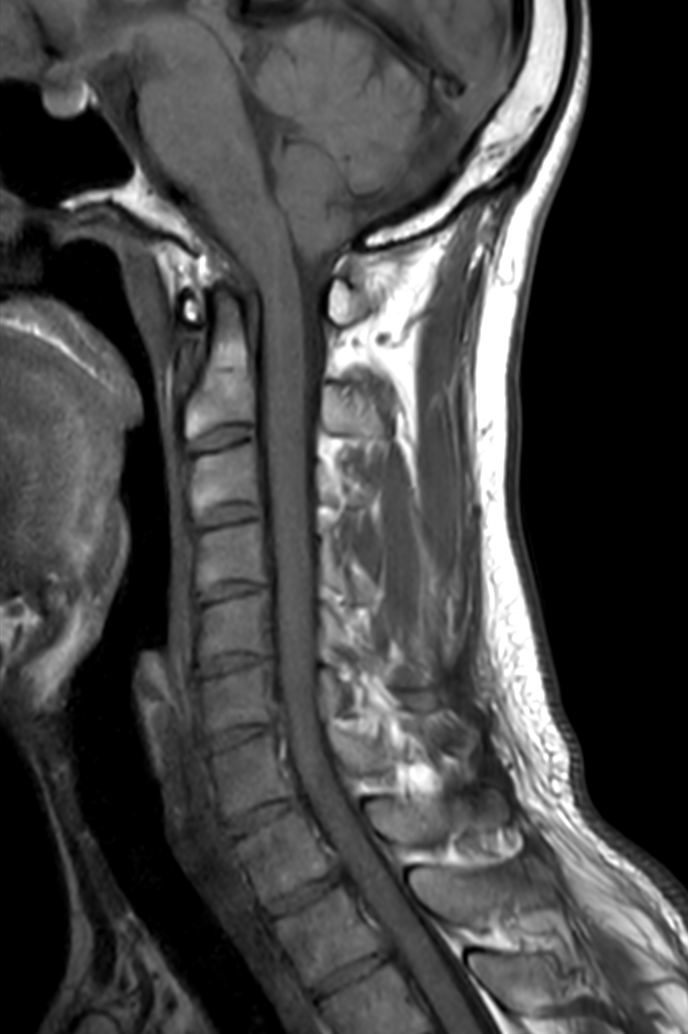

Sagittal T1w TSE - Compressed SENSE

Sagittal T2w TSE - Compressed SENSE